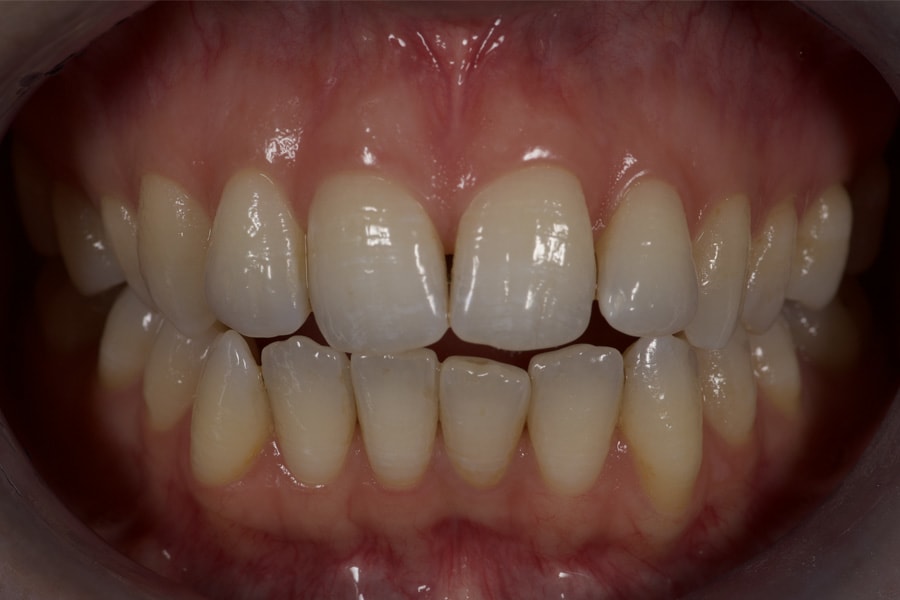

A 31-year-old female patient presented with the following intraoral conditions: an anterior open bite, bimaxillary crowding, negative crown torque, early “black triangles,” and a thin phenotype/biotype with early recessions. Her extraoral situation included a gummy smile with high-lip mobility, asymmetric arch forms and posterior corridors, and incompetent lip closure (Figure 2 through Figure 4). Collectively, these factors increase esthetic and periodontal risk and favor posterior intrusion over anterior intrusion.4-8,12-16

Treatment planning included the following key factors:

Airway/dentofacial: Preserve the anterior vertical; plan posterior intrusion to reduce display via mandibular CCW autorotation. (Figure 5 and Figure 6)

Biomechanics: Execute derotation/torque into the bone envelope; align the curve of Spee; maintain anterior clearance in the functional envelope.

Periodontium: Enable gentle forces; later, incorporate CTG to thicken the thin phenotype and cover recessions.4-8,12-16